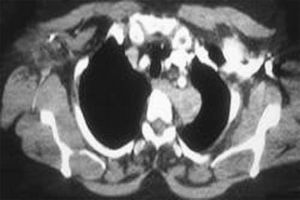

(一)X線按病期和疾病程度而異。早期或輕症患者可無異常發現,有時臨床表現和X線改變不相一致。典型病例急性期在中、下肺野見瀰漫性肺紋理增粗,或細小、邊緣模糊的散在小結節影。病變可逆轉,脫離接觸後數周陰影吸收。慢性晚期,肺部呈廣泛分布的網織結節狀陰影,伴肺體積縮小。常有多發性小囊性透明區,呈蜂窩肺。